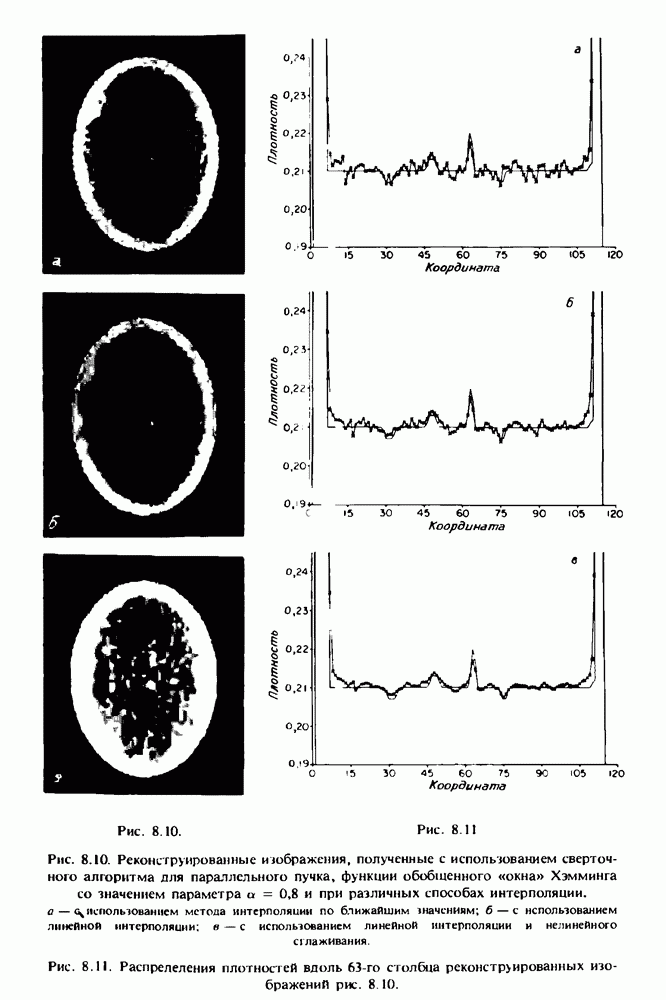

15.5. ЭКСПЕРИМЕНТАЛЬНЫЕ РЕЗУЛЬТАТЫ

Наш первый пример относится к случаю отображения системы желудочков головного мозга человека, которое было сделано по восьми смежным срезам толщиной На рис. 15.1 (вверху) приведены фрагменты из 80 х 80 элементов изображения трех из указанных срезов. Система желудочков изображена на фрагментах полностью. Размер элемента изображения в срезах составлял 1,5 х 1,5 мм, что соответствовало размеру элементарного

объема 1,5 х 1,5 х 8 мм, хотя более желательна, как и в предыдущих разделах, была бы кубическая форма элементарных объемов. Чтобы преобразовать элементарные объемы в кубические, использовалась линейная интерполяция данных для оценки 38 смежных срезов толщиной 1,5 мм. Таким образом, формируется массив из 80 х 80 х 32 чисел, характеризующих среднюю плотность множества элементарных объемов кубической формы.